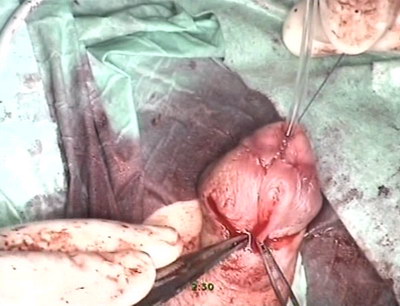

Уретра дренирована катетером Нелатона №8, последний Фиксирован

к головке и повязке. Асептическая наклейка с глицерином.